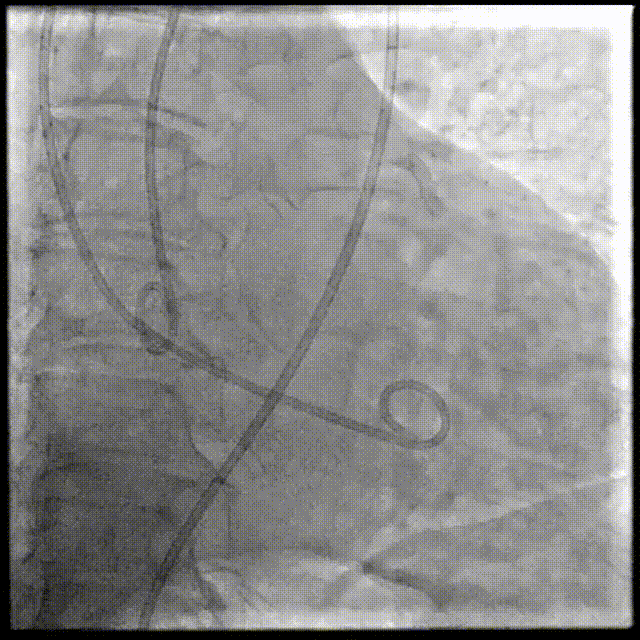

2026年伊始,TaurusTrio经导管主动脉瓣系统在武汉大学人民医院,中国科学技术大学附属第一医院,安徽医科大学第一附属医院,安徽医科大学第一附属医院北区,首都医科大学附属北京安贞医院南充医院,海南省人民医院等多家临床中心成功开展上市后全国首批植入。这不仅是TaurusTrio正式走向广泛临床应用的重要里程碑,更标志着中国单纯主动脉瓣反流介入治疗正式迈入了“心键合璧”的全新纪元。

岁末年初,十三省联动。TaurusTrio的问世,一举突破了主动脉瓣反流临床治疗的传统手段桎梏,将以标准化、规范化的临床操作体系为支撑,奔赴更广阔的临床一线,为千万主动脉瓣反流患者带来获益。让我们共同见证这灿烂的“首植”时刻,并期待更多的顶尖术者与原创器械的完美共舞,以创新之力共筑结构性心脏病诊疗领域的新未来。